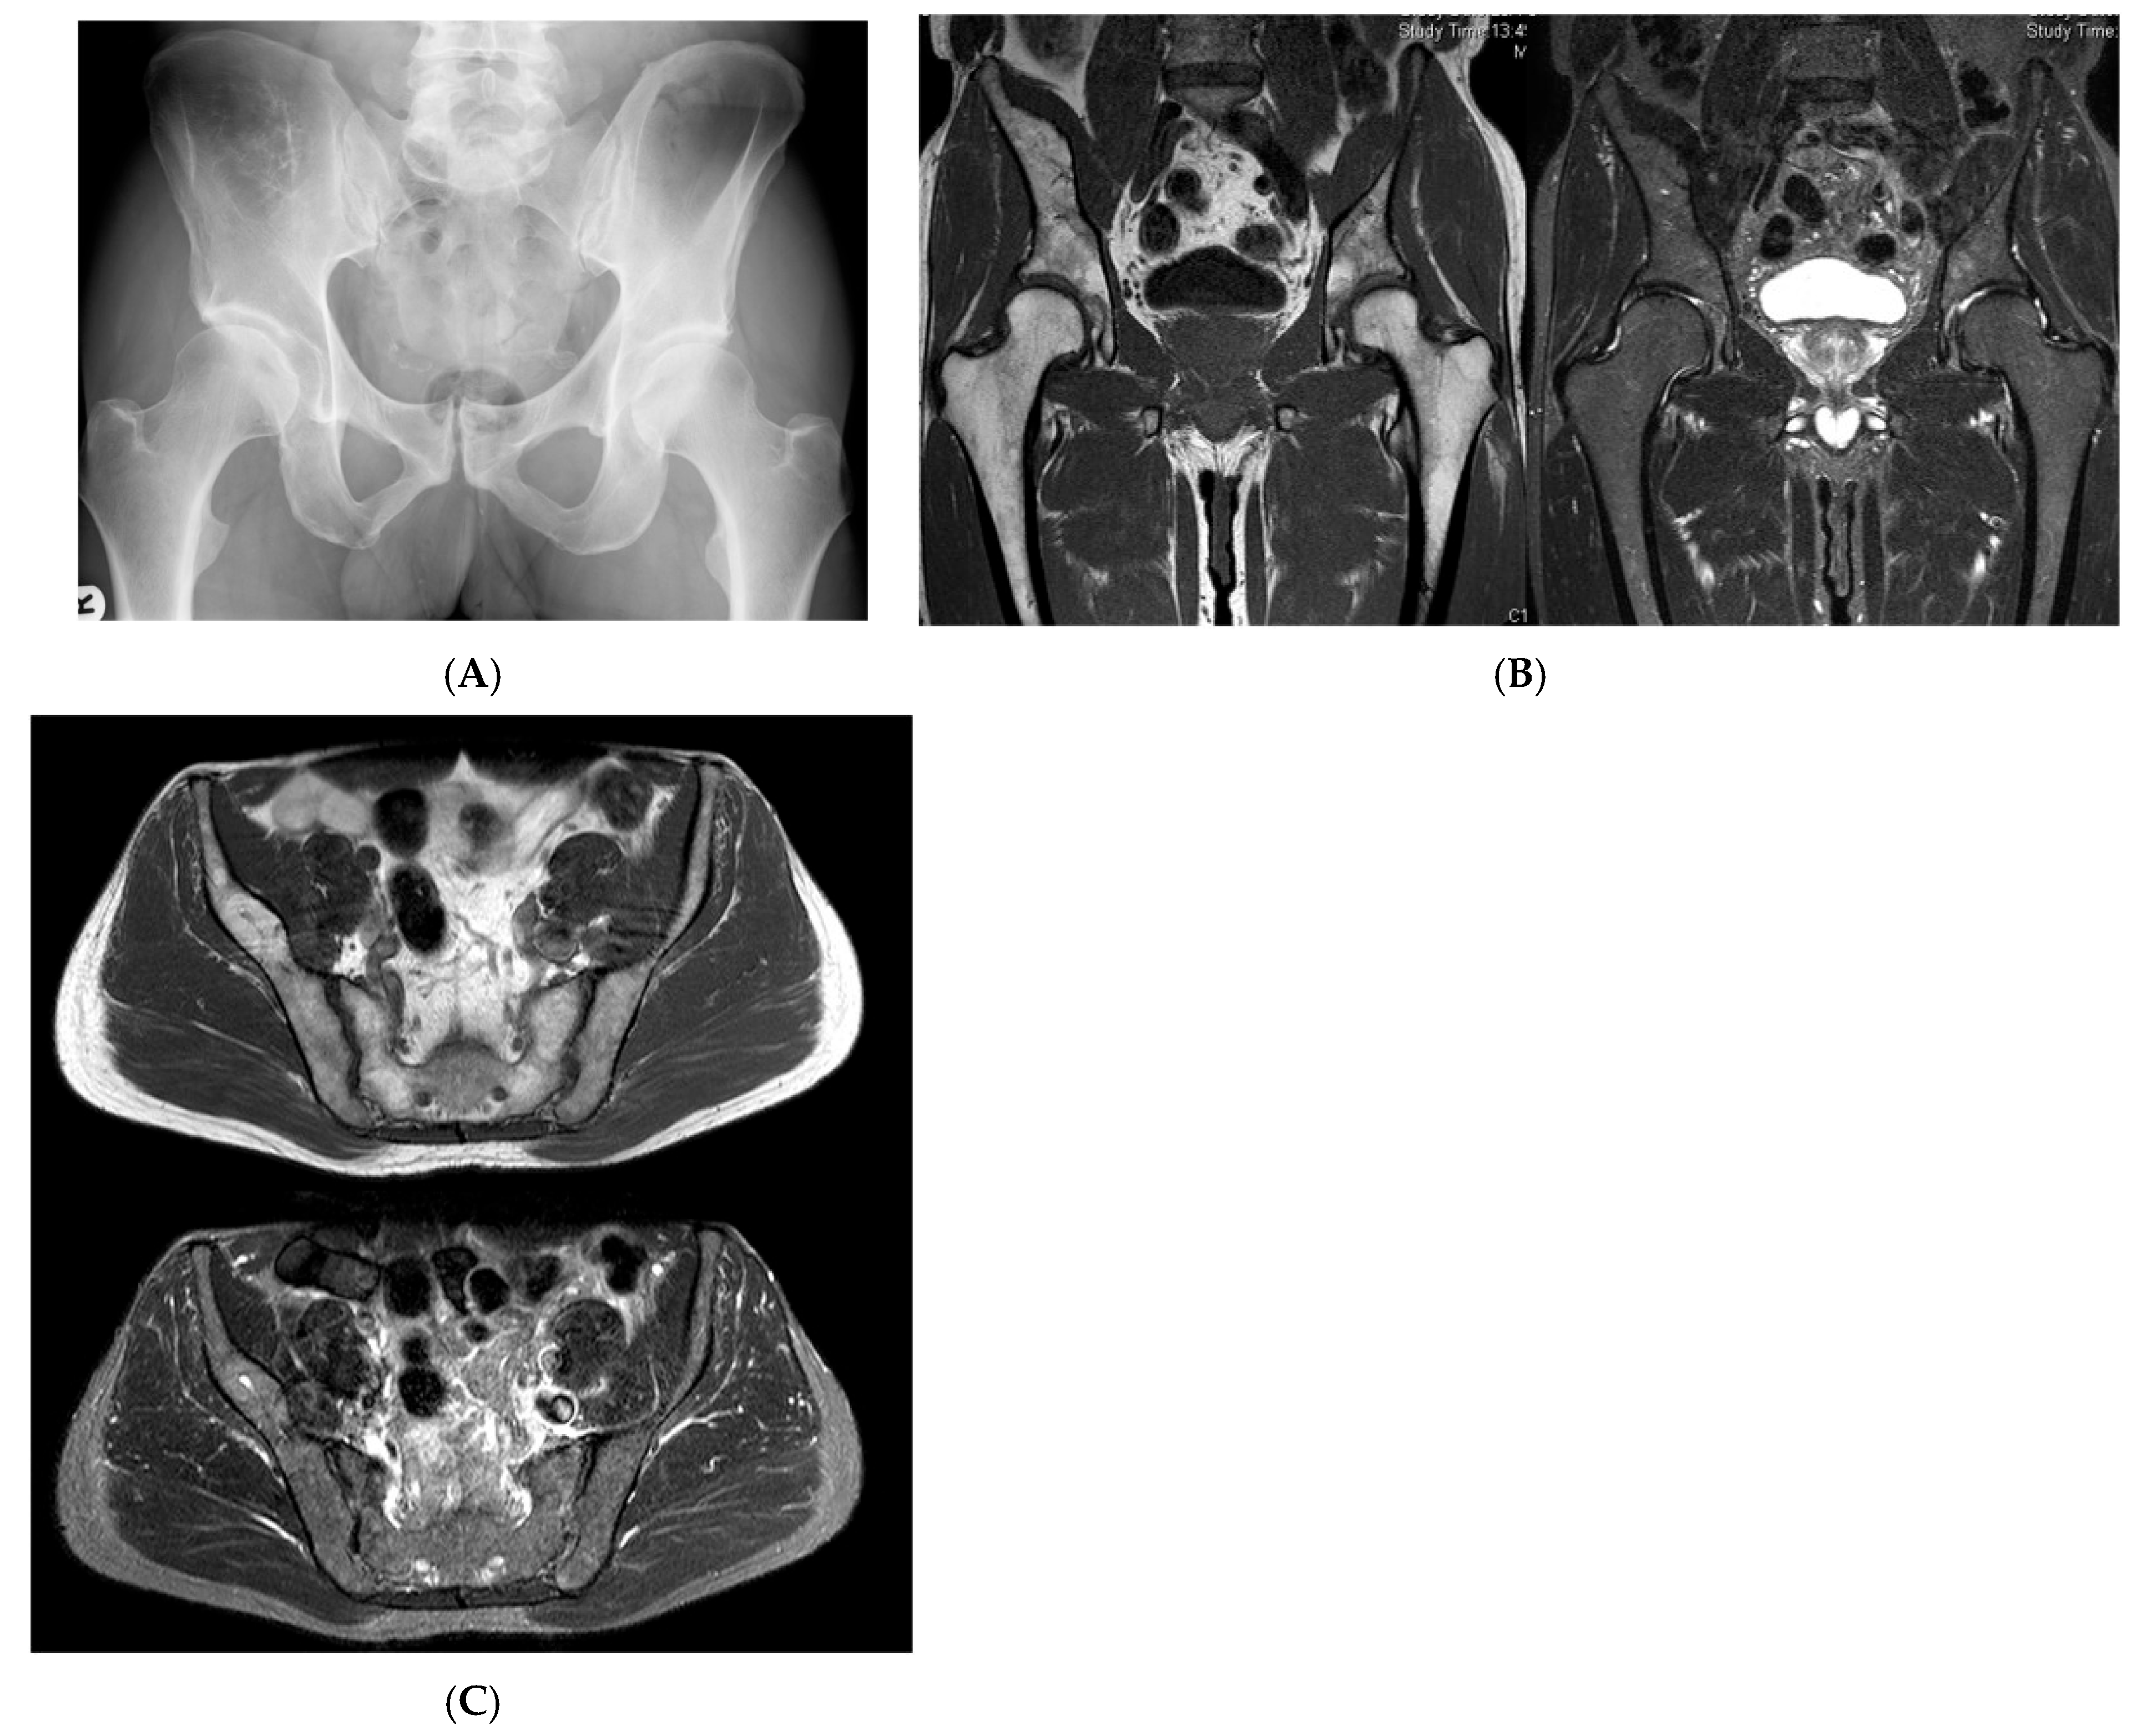

Figure 2.

Intraosseous lipoma, right iliac bone. (A) AP radiograph demonstrating a right iliac bone lesion. (B) Coronal TW1 and STIR MRI side by side, demonstrating a right iliac fat-containing bone lesion exhibiting fat suppression. (C) Axial T1W MRI showing a right iliac bone lesion and axial STIR MRI of the same lesion with fat suppression.